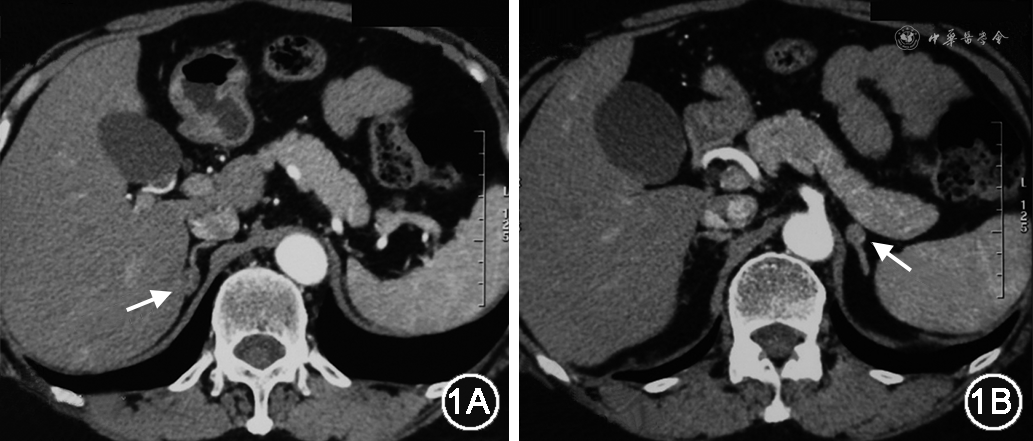

体格检查:体温36.3 ℃,脉搏86次/min,呼吸19次/min,卧位血压115/68 mmHg,立位血压102/67 mmHg。未见紫纹及瘀斑等异常体征。实验室检查:血钾正常3.93 mmol/L,血钠正常140.6 mmol/L,血二氧化碳正常29.7 mmol/L,血钙、磷正常;尿钾、钠、钙、磷正常。血、尿、便常规正常,肝功能、肾功能、凝血及肿瘤标志物正常。血糖、糖化血红蛋白、甲状腺功能、性腺激素、脱氢表雄酮正常。24 h尿醛固酮14.7 μg/24 h(1.19~28.10 μg/24 h)(括号内为正常参考值,下同),24 h尿游离皮质醇(UFC)332.3 nmol/24 h(98.0~500.1 nmol/24 h),促肾上腺皮质激素-皮质醇(ACTH-F)节律0点皮质醇356.09 nmol/L(0~165.7 nmol/L),午夜1 mg地塞米松抑制试验晨8点皮质醇55.69 nmol/L。血甲氧基酪胺<24 pmol/L(≤100 pmol/L),甲氧基肾上腺素98.8 pmo1/L(≤420.9 pmo1/L),甲氧基去甲肾上腺素138.5 pmol/L(≤709.7 pmo1/L)。肾素-血管紧张素-醛固酮系统评估,体位试验:卧位/坐位2 h/坐位4 h的直接肾素浓度(PRC)1.3/3.3/3.8 mU/L、血浆醛固酮浓度(PAC)27.2/28.0/24.7 ng/dl(1 ng/dl=27.7 pmol/L);坐位2 h的血浆醛固酮与肾素活性比值(ARR):8.5(阳性判断标准:ARR≥3.7[1]),提示该患者原发性醛固酮增多症(primary aldosteronism,PA)初筛阳性,醛固酮瘤可能(坐位4 hPAC较卧位PAC不升反降[2])。进一步行确诊试验:生理盐水试验前PAC为21.3 ng/dl,试验后PAC为13.8 ng/dl(阳性判断标准:试验后PAC>10 ng/dl[1]);卡托普利试验前PAC、PRC分别为17.5 ng/dl、3.1 mU/L,口服50 mg卡托普利片2 h后PAC、PRC分别为15.4 ng/dl、5.6 mU/L(阳性判断标准:试验后2 h PAC>11 ng/dl[3])。该患者确诊试验均支持PA。影像学检查:肾上腺增强CT(图1):双侧肾上腺小结节,考虑良性,皮质腺瘤可能性大。

继续PA分型诊断,并明确责任病灶。行地塞米松抑制联合ACTH兴奋试验:0点口服1 mg地塞米松后,晨8点ACTH明显被抑制,静脉推注ACTH 50 U后,60 min PAC达最高值44.2 ng/dl(阳性判断标准:ACTH兴奋后120 min PAC≥77.9 ng/dl,诊断单侧PA[4]),提示双侧肾上腺病变,不除外特发性醛固酮增多症(idiopathic hyperaldosteronism,IHA)。患者有积极治疗意愿,进一步行ACTH兴奋下的非同步双侧肾上腺静脉取血(adrenal venous sampling,AVS)(表1),计算侧别指数(LI)=(校正后)高侧醛固酮均值/低侧醛固酮均值比值=0.430/0.025=17.20,LI≥4.0提示左侧肾上腺醛固酮优势分泌[5]。同时,将AVS下腔静脉、左肾上腺静脉、右肾上腺静脉血标本和患者盐水输注前晨8点卧位肾素-醛固酮的外周静脉血标本,送检类固醇激素谱,据结果(表2)分析,左侧肾上腺病变考虑为醛固酮瘤(aldosterone-producing adenoma,APA)[6],右侧肾上腺病变考虑为无功能瘤。推荐行左侧肾上腺APA切除术,患者选择择期手术,予出院,出院诊断:原发性醛固酮增多症:左侧肾上腺APA,右侧肾上腺无功能瘤。出院后3周随访:降压药物调整为硝苯地平缓释片20 mg、1次/日,螺内酯 20 mg、2次/日;自测血压130/90 mmHg左右,无低血钾发生。